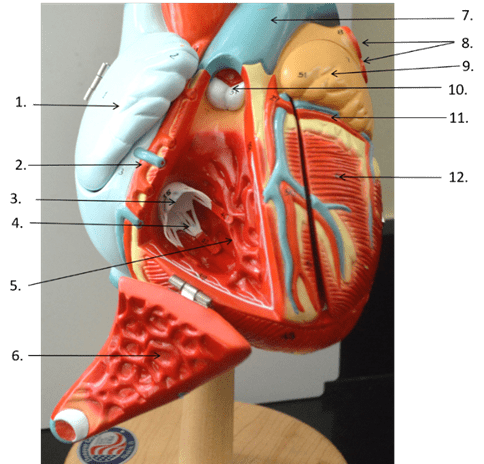

What two chambers of the heart are separated by this valve with two cusps?Give the name of the valve as well.

Blood passes through *this valve* as it moves from the right ventricle to ______.

pulmonary valve, pulmonary trunk

What cardiac chamber is in between the mitral valve and the aortic valve?

left ventricle

How many leaflets does the tricuspid valve have, and what is the correct medical term for the condition in which this valve fails to close properly, allowing blood to flow back into the right atrium during systole?

3, Tricuspid regurgitation or Heart murmur,

What are the "lub" and "dub" sounds heard during the heartbeat, and what do they represent respectively?

Heart Valves Closing, lub sound is when the AV valves shut, the dub sound is when the semilunar valves shut

A cardiologist receives a patient who is presenting with chest pain, fatigue, and shortness of breath. Upon examination, she finds that the valve between the lower left heart chamber and the body's main artery (aorta) is narrowed and doesn't open fully. What valve is this and what is the name of the condition and its resulting effect on blood circulation?

Aortic Valve, Type of Valve Stenosis (Aortic Stenosis). This stenosis reduces or blocks blood flow from the heart to the aorta and to the rest of the body.